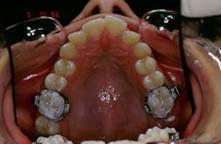

Pour finir j'etaits oblige de changer mon plan de traitement et accepter la solution par extraction de 4X4 et finir en classe I dentaire et legere tendance de classe II squelletique. L'ensemble du cas est tres acceptable, la patiente est tres contente, son sourir pas mal du tout, meme si ce n'est vraiment mon point de vu!!! Mais voila un cas ou j'etaits oblige d'extraire pour des raisons multiples, morphologie ethnique, maturation precoce, demande esthetique de la part de la patiente, des erreurs mecaniques de ma part? peut etre bien mais ca s'est passe comme ca... voici les photos

13 ipxuzs - Eugenol

14 f0gqim - Eugenol

15 myewxj - Eugenol

16 d66e2q - Eugenol